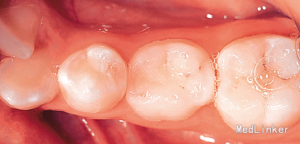

诊断:35牙缺失,牙列不齐 治疗:排齐整平上下牙列,对滞留的乳磨牙处理如下:因乳磨牙宽大,较正常前磨牙近远中径大很多,正畸治疗过程中逐次给乳磨牙减径后树脂修复参与正畸治疗,使减径树脂修复后的乳磨牙宽度为以后修复的前磨牙宽度一致。减径后的间隙留作牙列内其他牙齿的排齐。

2年正畸治疗结束后,乳磨牙仍在。一年以后,患者18岁成年,拔除乳磨牙,植入植体,半年后套冠,效果很好,患者满意。有些先天缺失第二前磨牙的患者,若第二乳磨牙比较健康,可以减径后树脂修复参与正畸治疗,这样有保存骨量,维持牙弓间隙,保持与对合牙功能接触以免对合牙伸长的作用。骨量的保存利于植体的植入。